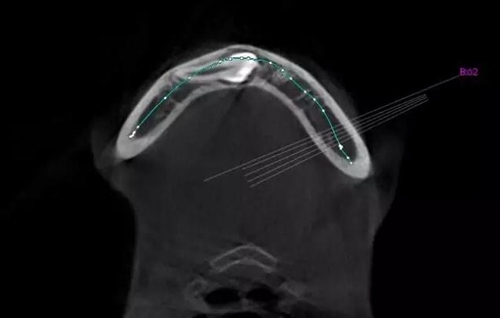

CBCT顯示